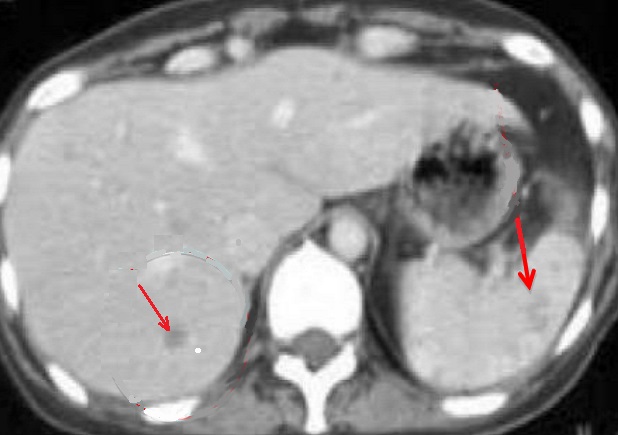

Aspect radiologique en oeil

de boeuf de type II de abces fungique de la

rate ( fleche rouge ) . La lesion peut en

s.observe dans le foie droit . Coupe TDM axiale avec

injection de contrast intraveineuse . |